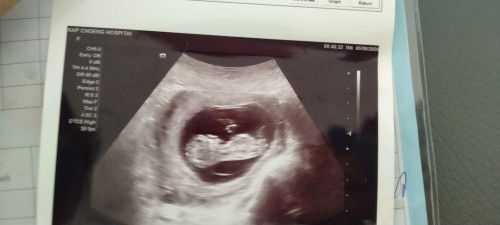

ของเราตอน10w+3

10weekจ้า